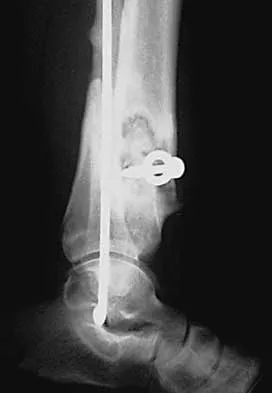

A 68-year-old woman who sustained a closed distal tibia fracture 2 years ago was initially treated with an external fixator across the ankle for 12 weeks, followed by intramedullary nailing of the fibula and lag screw fixation of the tibia. She continued to report persistent pain so she was treated with a brace and a bone stimulator. She now reports pain in her ankle. Examination reveals ankle range of motion of 8 degrees of dorsiflexion to 25 degrees of plantar flexion. She is neurovascularly intact. Current radiographs are shown in Figures 9a through 9c. What is the next most appropriate step in management?

Explanation